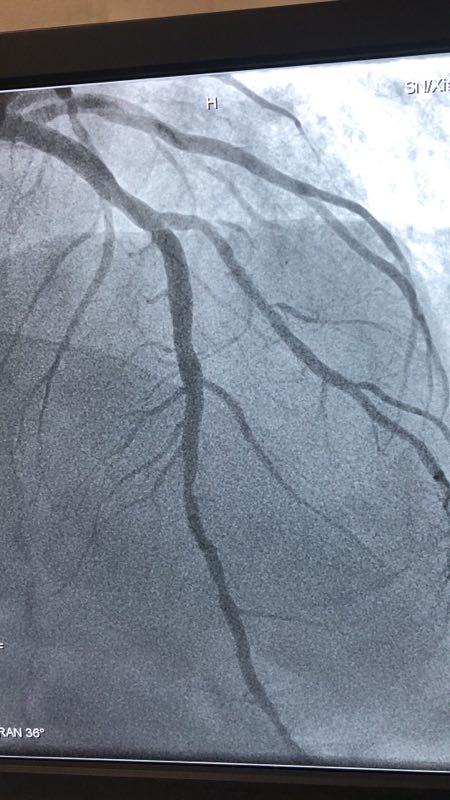

此例患者,男性,56岁,11年前因心绞痛在西京医院行冠状动脉造影检查后于D1对角支置入1枚支架治疗。术后患者口服“阿司匹林肠溶片、氯吡格雷、阿托伐他汀”等药物治疗1年后自行停药,并有长期大量吸烟史。2018年12月24日患者突发胸痛、胸闷,急来21点游戏攻略站 就诊。急诊行冠状动脉造影检查提示D1对角支原支架内再狭窄70%-90%。急救中心主任张誉洋副主任医师考虑到第一对角支管径较小,于原支架内再次置入支架引起再狭窄的风险极大,遂建议应用药物涂层球囊扩张术治疗D1对角支原支架内狭窄。与患者充分沟通后,于12月27日行冠脉药物涂层球囊PTCA术治疗,造影显示血管开通情况良好,术后患者症状明显改善。